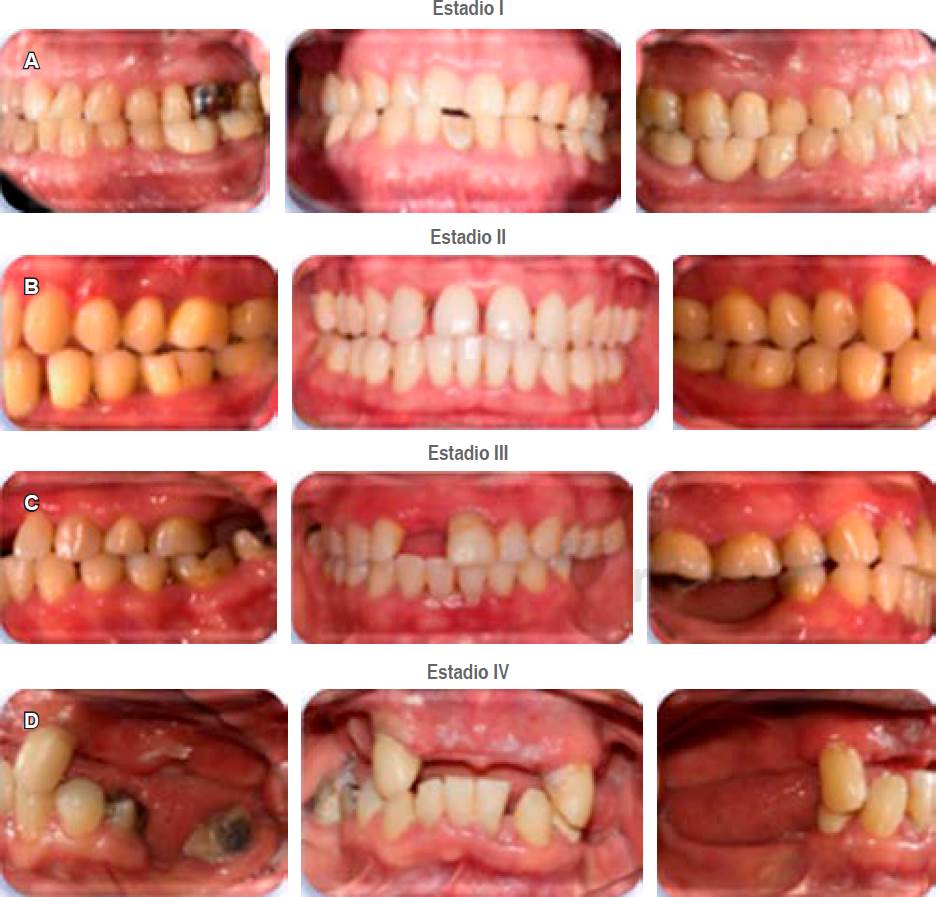

a. Estadios. Los diferentes estadios se basan en la severidad, complejidad, extensión y distribución de la enfermedad. El estadio I representa a la periodontitis inicial; el estadio II a la periodontitis moderada; el estadio III a la periodontitis severa con potencial para pérdida dental adicional; y el estadio IV a la periodontitis avanzada con potencial para pérdida de la dentición.19

En la Tabla 4 se muestran los parámetros a tomar en consideración para asignar cada uno de los estadios y la Figura 5 ejemplifica casos clínicos para cada estadio.